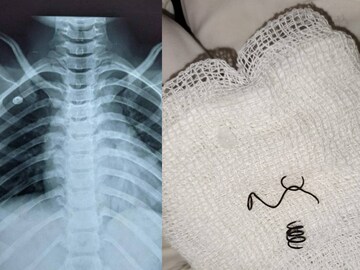

കണ്ണൂർ: പതിനൊന്ന് വയസ്സുകാരന്റെ ശ്വാസകോശത്തിൽ (Lungs)കുടുങ്ങിയ ലോഹനിർമ്മിത സ്പ്രിങ് (Metal spring)വിജയകരമായി പുറത്തെടുത്തു. സങ്കീർണ റിജിഡ് ബ്രോങ്കോസ്കോപ്പി ചികിത്സയിലൂടെ കണ്ണൂർ ഗവ.മെഡിക്കൽ കോളേജ് (Kannur Medical College)ആശുപത്രിയിലെ വിദഗ്ധർ സ്പ്രിങ് പുറത്തെടുത്തത്.

കാസർഗോഡ് കുമ്പള സ്വദേശിയായ 11 വയസ്സുകാരന്റെ ശ്വാസകോശത്തിൽ വലത്തേ അറയിൽ കുടുങ്ങിയ രണ്ടു സെന്റീമീറ്ററോളം വലിപ്പമുള്ള സ്പ്രിങ് ആണ് നിക്കം ചെയ്തത്. മുമ്പെപ്പോഴോ അബദ്ധത്തിൽ കുട്ടി വിഴുങ്ങിയതാണിത്. മൂന്ന് കഷ്ണങ്ങളായി മാറിയതിനാൽ അതിന്റെ പ്രതിസന്ധിയും ചികിത്സാഘട്ടത്തിൽ അഭിമുഖീകരിക്കേണ്ടിവന്നു.

ശ്വാസകോശത്തിൽ സ്പ്രിംഗ് കുടുങ്ങി ആ ഭാഗം അടഞ്ഞു കിടന്നതിനാൽ കഫം ഉൾപ്പടെ കെട്ടിക്കിടന്ന് അണുബാധയും ഉണ്ടായിരുന്നു. മെഡിക്കൽ കോളേജിൽ കുട്ടിക്ക് അടിയന്തര ചികിത്സ ലഭ്യമാക്കി. അത്യാധുനിക ക്യാമറ സഹിതമുള്ള റിജിഡ് ബ്രോങ്കോസ്കോപ്പി ചികിത്സയിലൂടെ കുടുങ്ങിക്കിടന്ന സ്പ്രിംഗ് നിക്കം ചെയ്യാനായി. അണുബാധയുടെ തുടക്കമായ കഫവും നീക്കം ചെയ്തു. തുടർന്ന് രണ്ട് മണിക്കൂർ നേരം കുട്ടിയെ നിരീക്ഷണത്തിൽ വെച്ചു.